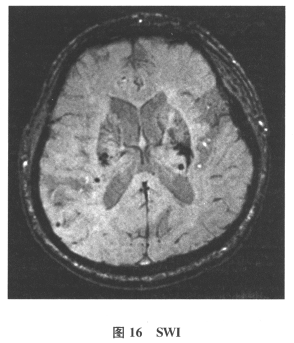

[多选题]患者男,61岁。因“发作性头晕2年,加重伴记忆力下降、走路不稳3月余”就诊。查体:BP140/70mmHg;意识清楚,构音障碍,近期记忆力及远期记忆力